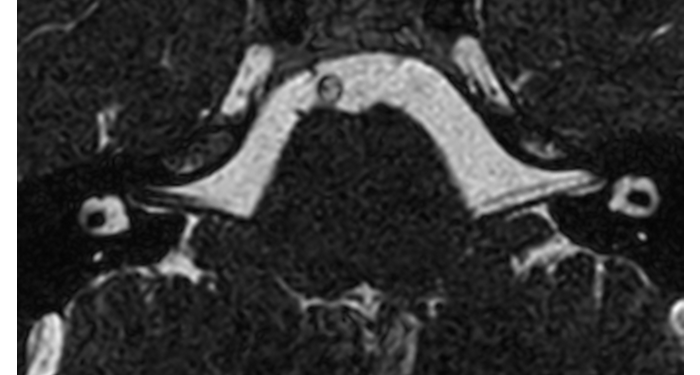

70% of radiologists consider neuro indications to be challenging, mostly due to a lack of appropriate imaging and visualization techniques¹. Philips aims to provide the best possible diagnostic clarity and treatment guidance for all patients with neurological disorders. By leveraging our dStream digital platform, this year, we are introducing, a set of novel imaging and visualization strategies. These may empower you to resolve complex neuro questions with more certainty, as well as unlock new neuro territories in advanced Neurofunctional applications. This is a key step towards elevating neuro diagnostics and ultimately touching more lives with MR imaging. ¹ TMTG Market Survey 2016

New neuro applications

MRI coils

Discover how Philips can help you select the right MRI coils that suit your imaging needs. Learn more about our different MRI coils.